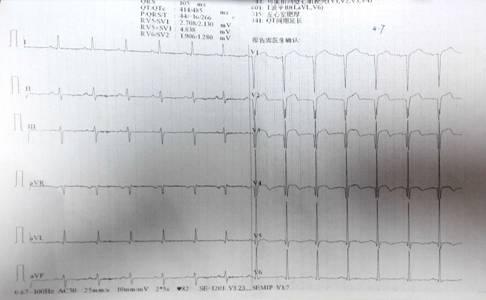

现病史:患者亲人代诉患者7天前突发胸闷、胸痛,其症状呈胸骨中下段压榨感,持续未缓解,无肩背部放射痛,不伴出汗,无头晕、恶心、反酸、嗳气等不适。遂立即至“新宁崀山医院”就诊,途中含服硝酸甘油症状未缓解,经心电图检查提示“1.窦性心律 2. 急性前壁心肌梗死 3.肺型P波 4.左室面高电压5.ST-T改变 肌钙蛋白示微阳性”,诊断冠心病,急性前壁心肌梗死,心功能III级,立即予以溶栓术(尿激酶150万U),术后予以抗凝、扩血管、降压(具体用药不详)后,患者症状较前稍好转。2天前患者开始出现咳嗽、咳痰,痰中带血,色鲜红,量不多,无血凝块,胸闷、胸痛较前好转,夜间有阵发性呼吸困难,无头晕、头痛,无恶心、呕吐、无黑便等症状;伴咽痛,为求进一步诊治,遂至我院急诊就诊,诊断为“1.冠心病 急性前壁心肌梗死 心功能III级(killip分级)溶栓术后 2.肺部感染 3.支气管扩张 4.高血压1级 高危组”,予以莫西沙星抗感染、前列地尔改善循环、泮托拉唑护胃、硫酸氯吡格雷片抗血小板后,患者症状稍缓解,为求进一步诊治,急诊以“冠心病 急性前壁心肌梗死 心功能III级(killip分级) 溶栓术后”收入我科。

患者未诉胸闷,活动后无明显气促,生活自理,查体:BP 110/70mmhg,双肺呼吸音清,无罗音,心率60次/分,律齐,心音可。双下肢无浮肿。

WBC 6.45×109,HB130g/l,PLT183×109

NT-PRO-BNP886.6pg/ml

K 4.55mmol/l ,NA144mmol/l ,CL114mmol/l

GLU 5.47mmol/l

BUN9.6mmol/l CR118umol/L , UA448umol/L